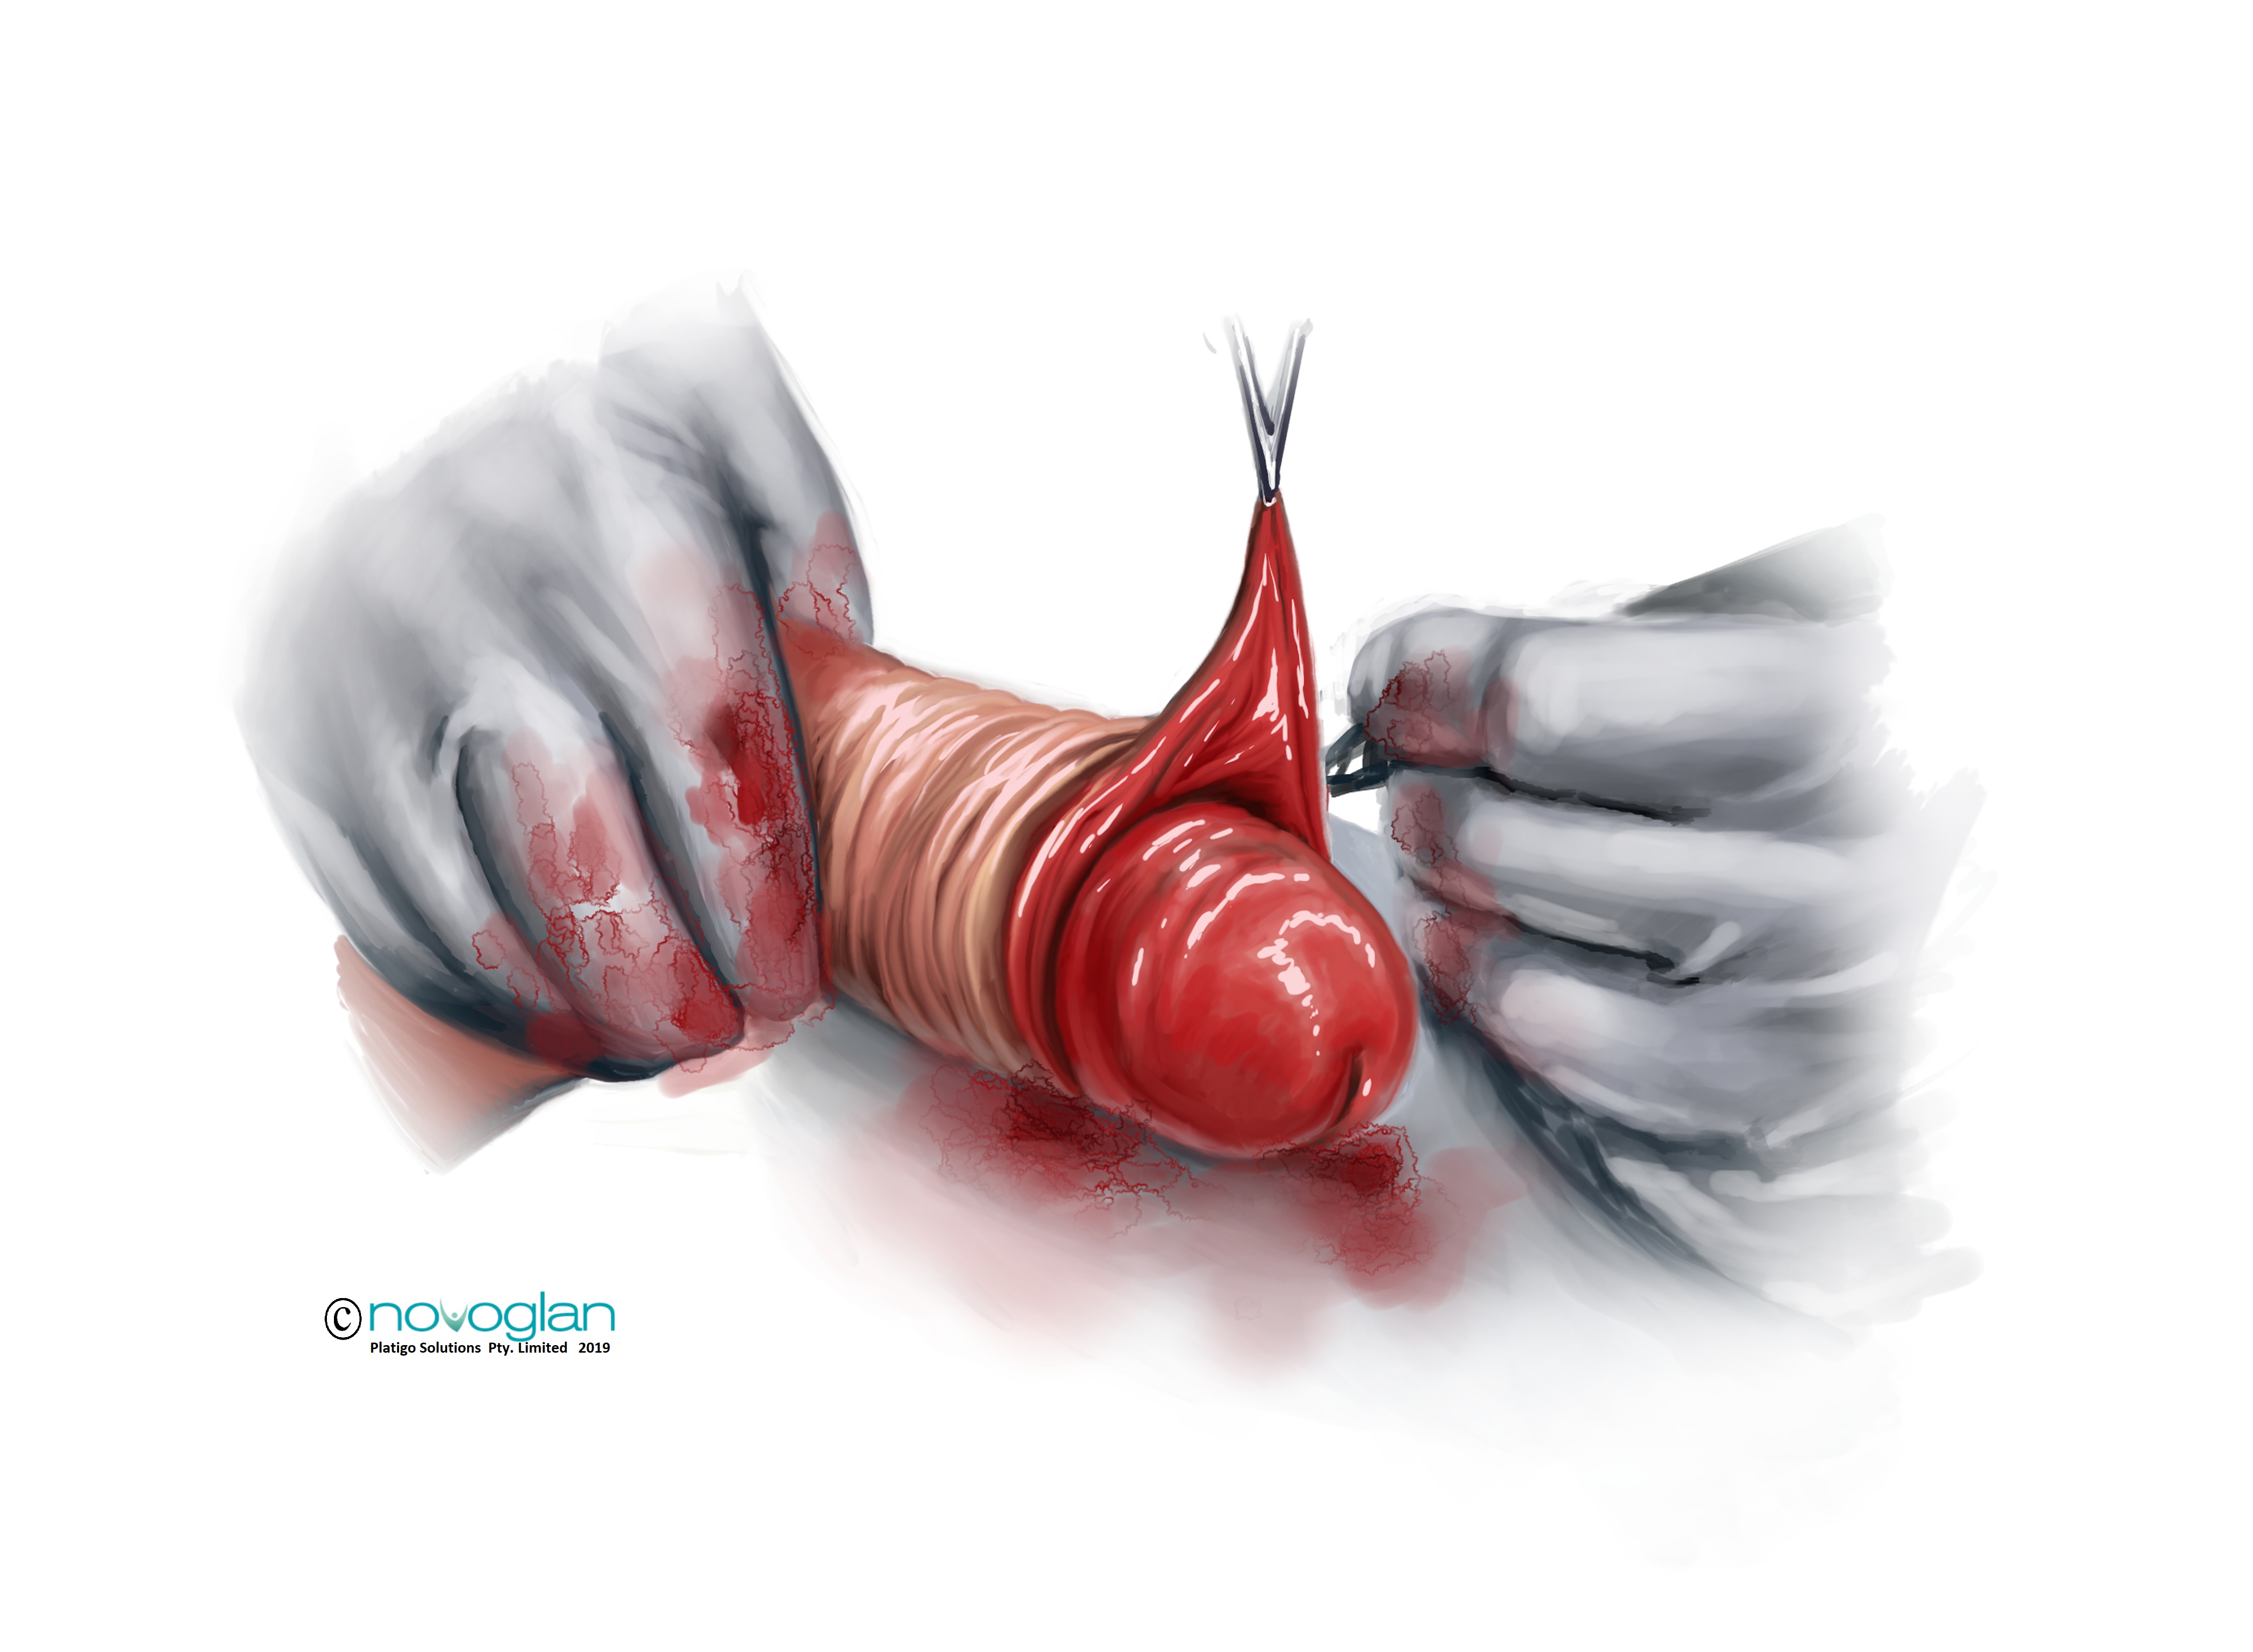

4: Paraphimosis of the Foreskin

Paraphimosis is generally considered a medical emergency whereby the foreskin of an uncircumcised man is retracted and becomes stuck along the shaft of the penis. This results in abnormal compression of the underlying tissues and restricting blood flow and lymph tissue function. Untreated, this can lead to gangrene and amputation of the glans penis. Quite clearly, amputation of the glans penis is not an ideal outcome for a man and that is why it is very important that if you suspect that you or someone you know has paraphimosis then you need to get them to emergency medical care without delay.

Paraphimosis can occur spontaneously or it can occur during treatment of phimosis when a man prematurely tries to retract the foreskin before enough new foreskin tissue has grown.

Treatment of paraphimosis usually requires surgical intervention including cutting of the foreskin to release the built-up fluid and in certain circumstances the complete amputation of the foreskin, that is circumcision.